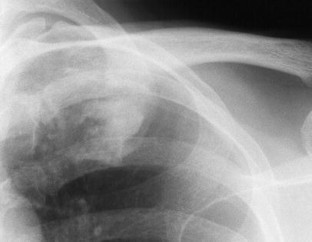

The SAPHO syndrome was a term coined to include a variety of musculoskeletal disorders associated with skin conditions, mainly palmoplantar pustulosis and acne conglobata. It is more correctly a spectrum which includes the following: skin lesions, osteoarticular manifestations of synovitis hyperostosis and osteitis affecting particular target sites, and·a clinical course marked by relapses and remissions. The major sites of involvement are the anterior chest wall, the spine, long bones, flat bones, and large and small joints. The distribution and severity of involvement varies from the adult to the pediatric form of chronic recurrent multifocal osteomyelitis (CRMO). The diagnosis of SAPHO syndrome is not difficult when the typical osteoarticular lesions are located in characteristic target sites. The diagnosis is more difficult if atypical sites are involved and there is no skin disease.

Fig. 7.